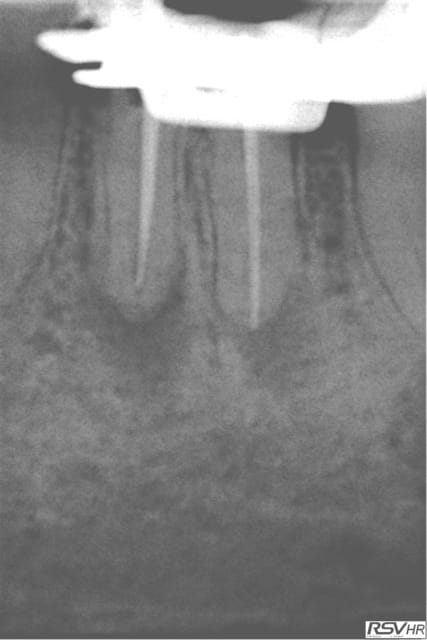

Tu peux me faire un CBCT de 35 ? Il semble y avoir un 4ième bien que le tt endo soit correct.

Je viens de faire une bio sur 45 (pulpite). Et je crois que j'ai ma petite idée sur la cause du 4 ième de 35. -)

Capture d e cran 2016 02 10 10.04 - Eugenol

Capture d e cran 2016 02 10 10.05 - Eugenol